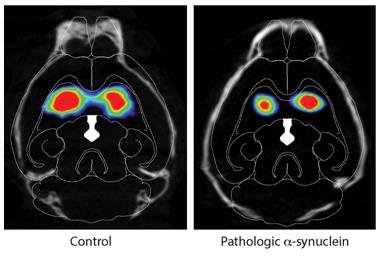

右图为α-突触核蛋白注入小鼠肠道后的DAT扫描,左图为对照组。图片来源:Ted Dawson

为了验证这一点,在最新的研究中,Ted Dawson博士和他的同事HanseokKo博士等将实验室中合成的错误折叠的α-突触核蛋白注入数十只健康小鼠的肠道中,并对注射后1个月、3个月、7个月和10个月的小鼠脑组织进行取样和分析。在为期10个月的实验过程中,研究人员发现,α-突触核蛋白开始在迷走神经与肠道相连的地方积聚,并继续扩散到大脑。

研究人员随后切除了一组小鼠的迷走神经,并将错误折叠的α-突触核蛋白注入其内脏。经过7个月的观察,研究人员发现,迷走神经断裂的小鼠没有发现细胞死亡的迹象。Dawson表示,切断的神经似乎可以阻止错误折叠的蛋白质的进展。